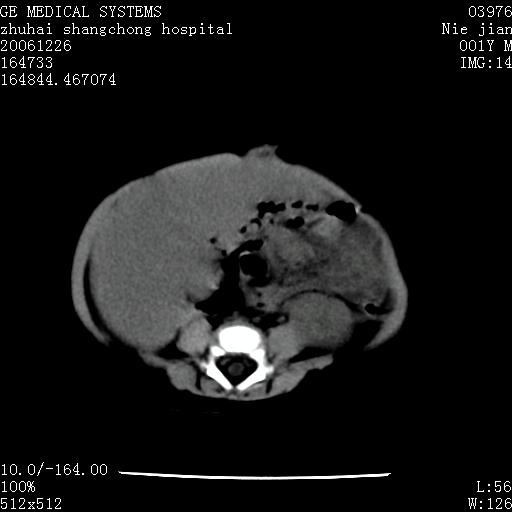

3个月婴儿腹胀来看。

【临床特点】

婴儿,腹胀,无特殊症状,未提供详细资料。

【影像特征】

1、肝明显增大,肝弥漫性低密度灶。

2、肾上腺区见类圆形肿块,其内密度不均,见片状偏高密度。

【诊断】

1、肝弥漫性病变,考虑急性肝炎致广泛脂肪浸润可能性大。

2、肾上腺区占位,假性肿瘤?肾上腺血肿(感染所致)?

一年后

1、肝硬化,脂肪浸润消失。

2、假性肿瘤消失或血肿吸收。

【分析】

1、关键着眼点:肝脏弥漫性病变内有没有走形的血管,仔细看部分低密度内有血管影(要有增强扫描作为证据就好了),说明并非肿瘤样病变,而是脂肪浸润。即可能不是转移瘤或原发肿瘤,低密度的形态上看,是片状,也不像肿瘤。

2、儿童肝炎最常见的是感染,有时食入性损害或药物也可致肝脏炎症,肝炎致大空泡型脂肪变性,是一种无痛性疾病,无症状,病因有营养异常、代谢性疾病、药物及病毒感染。所以脂肪变性与感染有关。

3、肝炎的结局是肝硬化,而恰恰一年后复查,已有肝硬化表现。肿瘤一般那会消失,那叫奇迹。

4、肾上腺出血也可见于败血症及感染,通常包块在数周内消失,ct表现包块内有偏高密度,可能是亚急性血肿的表现。假性肿瘤即腹部肠管积液、扩张血管及邻近结构的伪像。自然会消失。

5、因此,感染可以贯穿一切,解释一切。肿瘤自然消退?可能吗?那些应要无道理的创造奇迹的事情会那么容易发生吗?